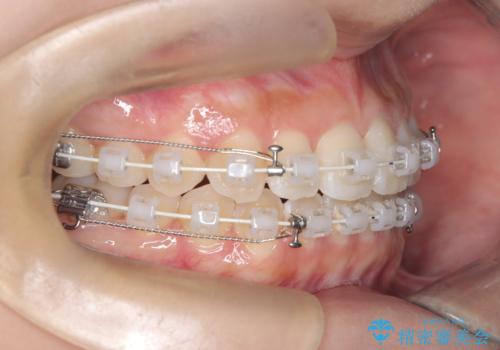

- 患者様は、上の前歯に翼状捻転(歯が回転して生えている状態)があり、全体の歯並び(叢生)の改善を希望して来院されました。診断の結果、非抜歯での治療が可能であると判断し、上顎にリンガルアーチを装着し、矯正用アンカースクリューを併用することで臼歯部を確実に遠心移動させる治療計画を立案しました。これにより、スペースを確保しつつ、前歯をきれいに並べることを目指しました。

治療では、審美ワイヤーを使用し、目立ちにくく配慮しながら矯正を進めました。上顎にリンガルアーチと矯正用アンカースクリューを用いて臼歯部を安定的に遠心移動させ、歯列全体のスペースを確保しました。その後、回転していた前歯を正しい位置に配列し、全体的な歯並びの改善を行いました。治療中は、装置の適切な管理と口腔衛生を徹底することが重要でした。結果として、見た目だけでなく機能的にも優れた歯列を実現することができ、患者様にもご満足いただけました。